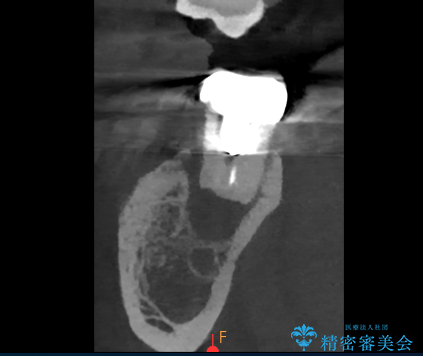

- 過去にヘミセクションが行われていたと思われる左下7番は、大きな歯根嚢胞および根尖病変が認められ、さらに骨縁下カリエスを伴っており、歯肉には瘻孔が形成されている状態でした。

保存は困難と判断し、左下7番は抜歯即時インプラントによる治療を行いました。